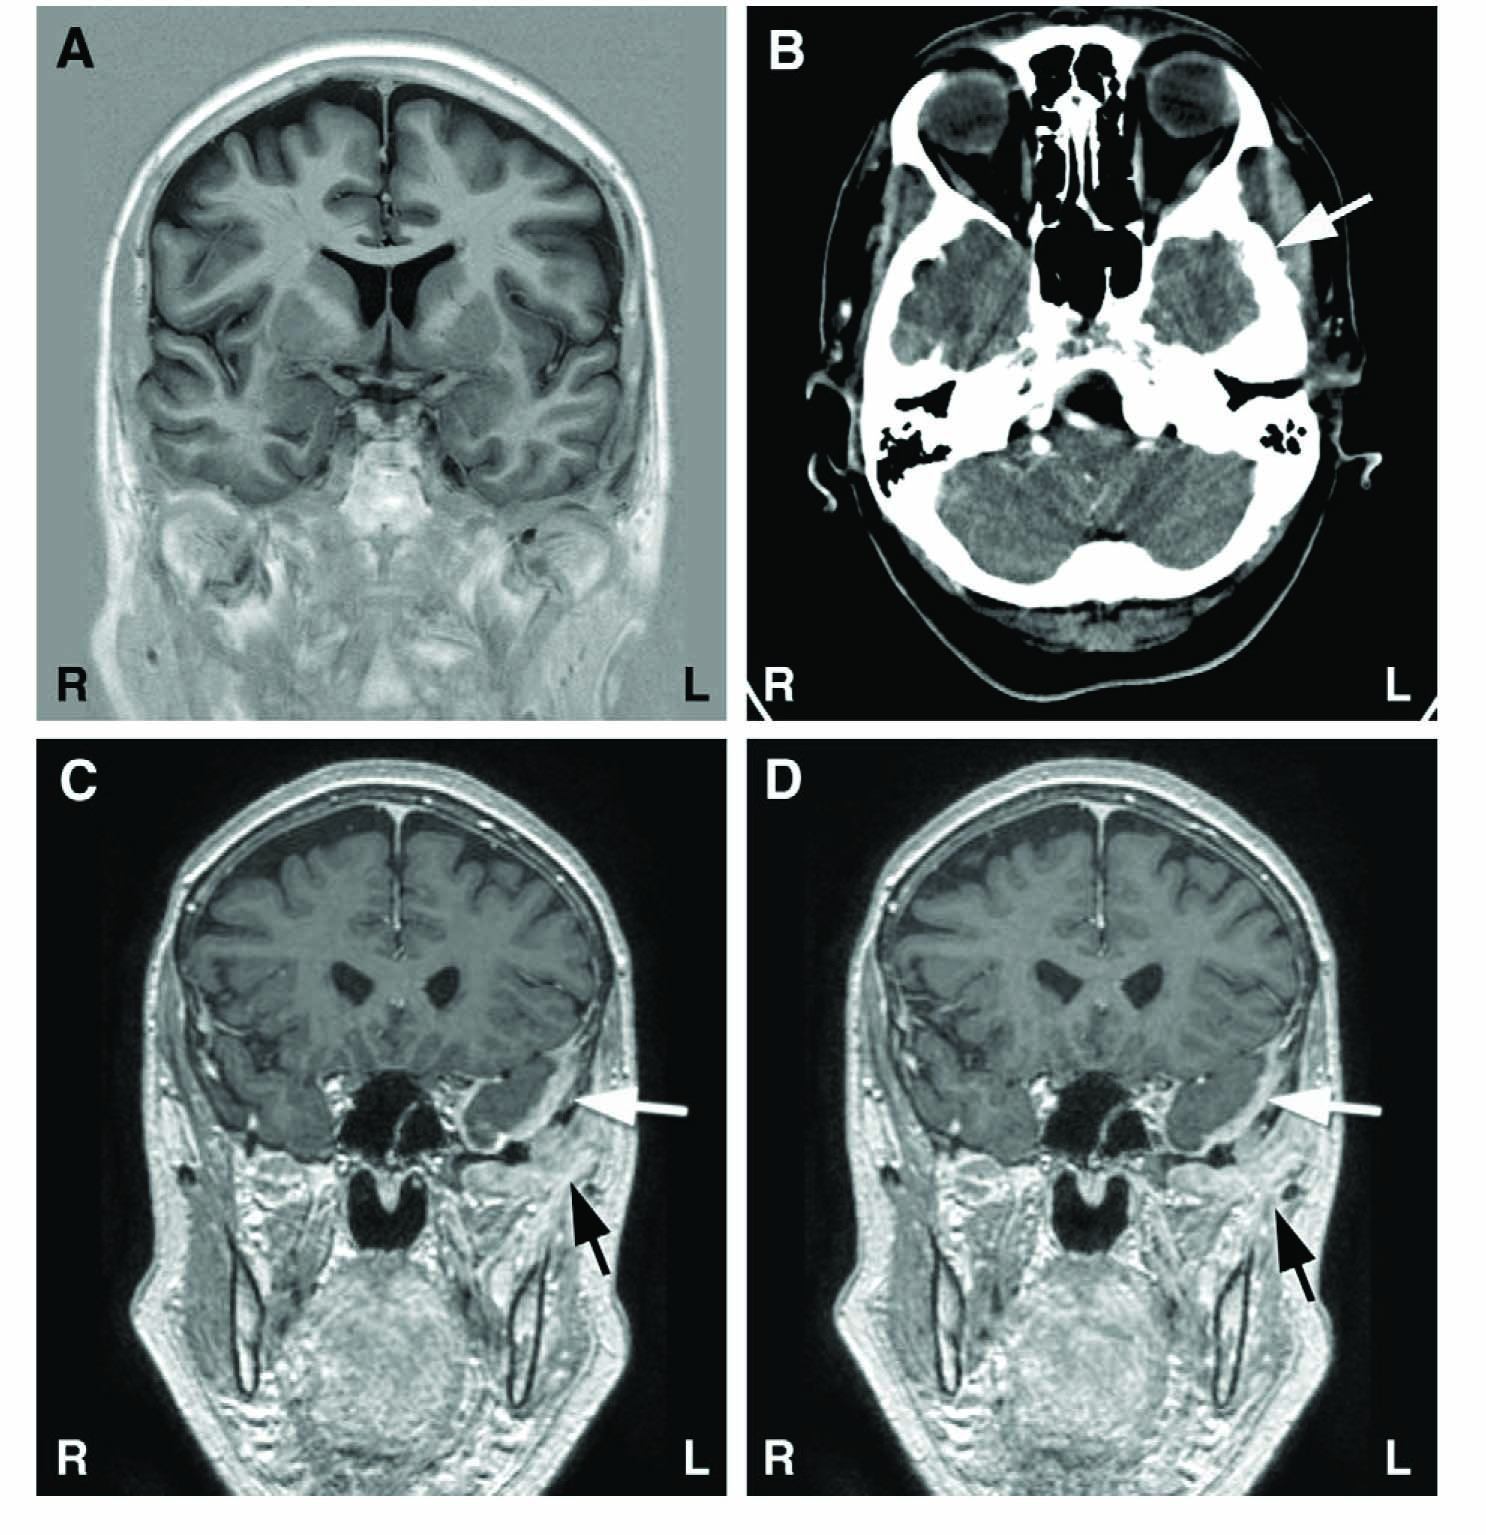

Results of structural brain imaging during the course of the disease. (A) Normal native MRI of the brain taken 4 months after onset of facial pain symptoms. (B) CT image taken 10 months after symptom onset with brain window setting; incipient lytic process of low temporal bone on left side marked with an arrow (hardly visible at this magnification). (C and D) Eleven months after symptom onset, gadolinium enhanced T1-weighted MR images show clearly visible pathologic enhancement of dura (white arrows) and enhancing soft tissue metastatic mass below temporal bone (black arrows).

A 63-year-old woman in good general health developed acute, severe facial pain, first located behind the left eye. She had a history of ductal breast cancer (T1N0M0G2) successfully treated 8 years earlier. Her deep aching pain was continuous spreading over time to the entire left side of the head. There were atypical neuralgic exacerbations lasting for up to 30 min with continuous smarting pain, numbness and paresthesia on the lower left side of the face and the tongue. The patient reported slowly progressive chewing difficulties, restricted mouth opening, and fluctuating eyelid edema. She was treated by a private neurologist during the first 8 months, with diagnoses of acute idiopathic trigeminal neuropathy, atypical facial pain, and trigeminal neuralgia. An ophthalmologic examination and brain MRI (Fig. 1A) had been normal at 4 months after symptom onset. Gabapentin 600 mg/day partially relieved the pain. Because of progressive chewing difficulties and suspected ptosis, she was referred to the University Hospital of Turku for further investigations to exclude myasthenic syndrome.

The first MR imaging performed at the private clinic had been normal (Fig. 1A), excluding also temporal arteritis. After neurophysiologic examination, native and enhanced CT (Fig. 1B) scans of the brain were done with routine brain protocol including a bone window, and they were interpreted as normal. Because of the neurophysiologic findings and progressing clinical symptoms, a new MRI scan covering the brain and the basal cranial bones was done with gadolinium enhancement 11 months after symptom onset. MRI showed increased meningeal enhancement in the region of the left temporal pole and base (Fig. 1C and 1D); a metastatic tumor mass invaded the basal parts of the temporal bone extending to the left orbit. A biopsy confirmed the metastasis of an adenocarcinoma. Residual tumor growth was also found in the operated left breast area.

The neurophysiologic tests currently available enable detailed analysis of trigeminal system pathology, providing good topographic-level diagnosis [1,2,9,10], and aiding in the difficult clinical assessment of neuropathic facial pain [2,5,7,11,12]. This good diagnostic accuracy was evident in our patient, but the neurophysiologic findings were probably not fully utilized in the initial analysis of the CT scans, interpreted as normal. At retrospective inspection of the same scans with high resolution and magnification, bony lytic invasion of the temporal bone could be distinguished by a specialist in neuroradiology (Fig. 1B).